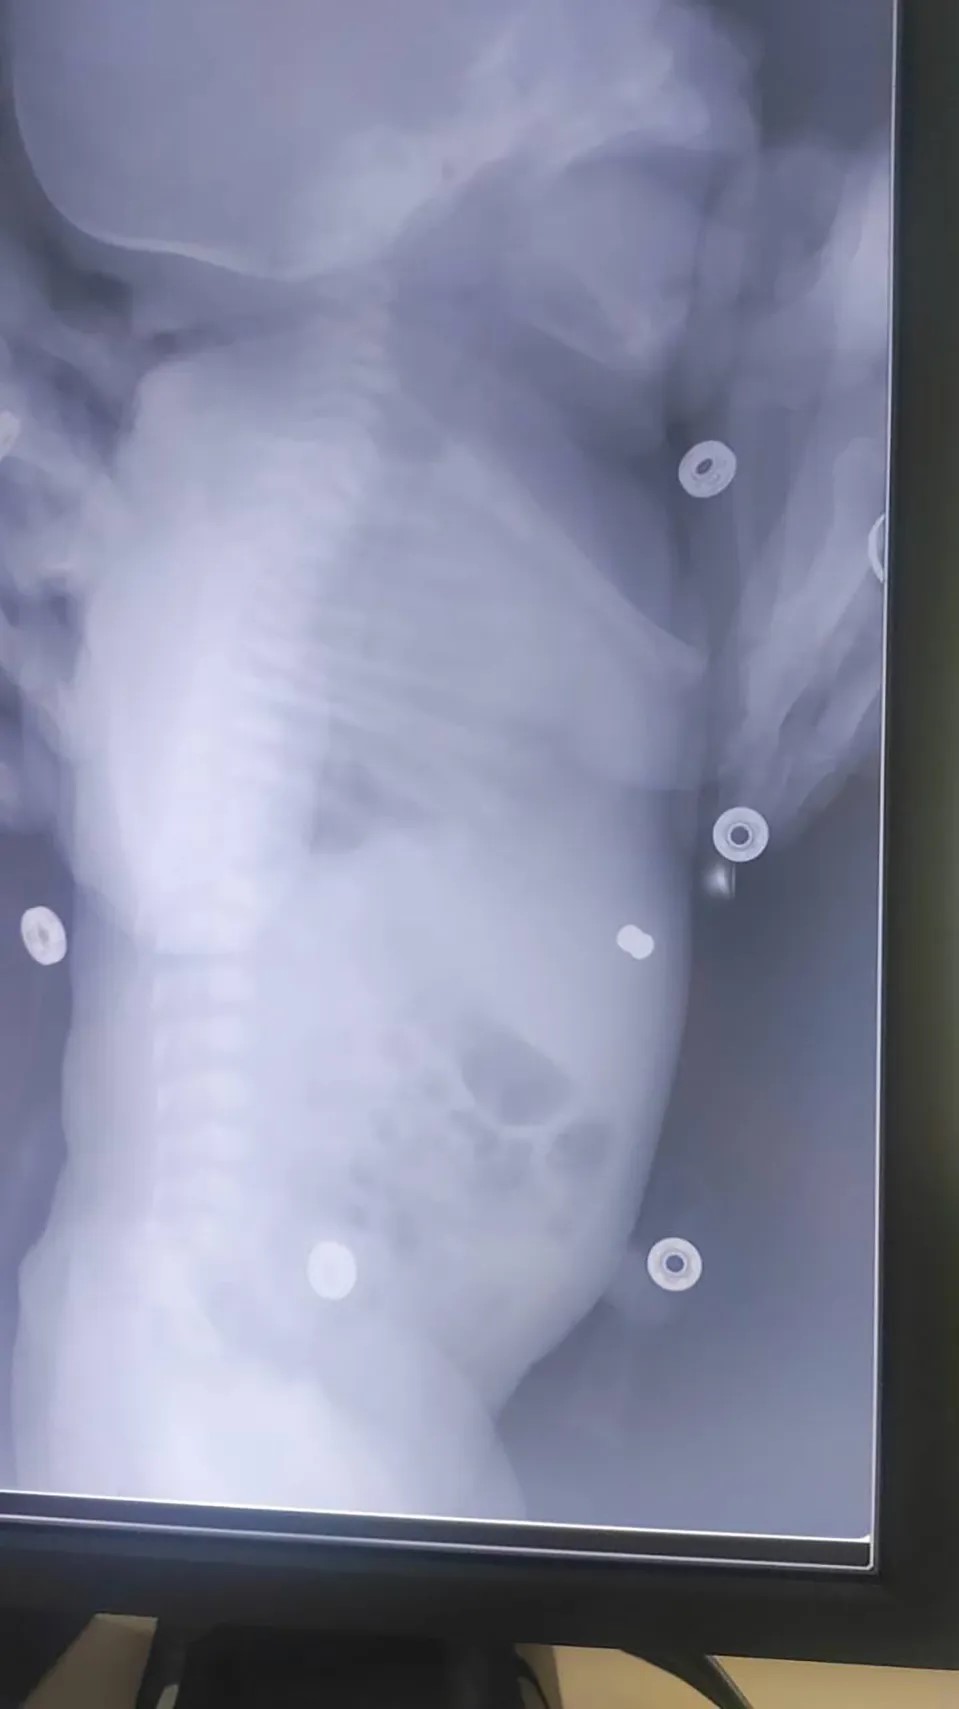

扫描结果显示,有一颗长度小于1厘米、宽度小于半厘米的子弹,卡在了孩子的前腹壁皮下。

(卡在婴儿腹部的子弹)

不过幸运的是,子弹的位置非常浅,并没有伤及孩子的重要器官,因而不会对性命和健康造成威胁,母亲也一样平安无事。

(子弹位于婴儿的前腹壁皮下组织)